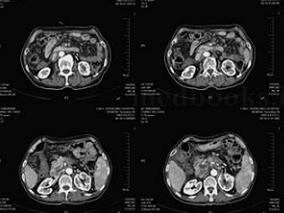

1小时条评论【病例介绍】 男,38岁。两年余前无明显诱因出现左上腹隐痛,伴轻度腹胀,无腹泻、便秘,无恶心、呕吐,无寒战、高热,未予特殊诊治。1周前自觉上述症状略加重,遂就诊外院,行腹部超声检查提示左上腹腹主动脉旁混合性包块,考虑腹膜后来源,进一步行上腹部增强CT提...